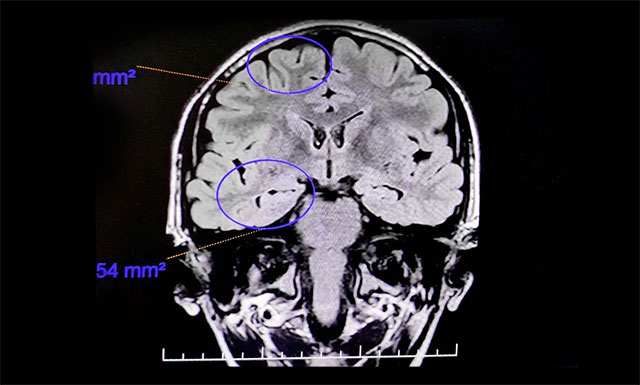

童童入院后,接受了一系列检查,行24小时长程脑电图监测,提示异常脑电图。PET/MR提示:患者右侧颞前叶内侧及杏仁体、海马区代谢较左侧减低,右侧海马略萎缩,考虑致癫灶可能。

▲ 通过系列检查评估,最终明确患者致癫灶